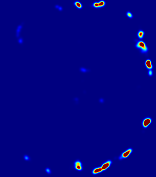

LesionRefer to captionRefer to captionRefer to captionRefer to captionRefer to captionRefer to caption𝐕rgbsubscript𝐕𝑟𝑔𝑏{\bf{V}}_{rgb}Refer to captionRefer to captionRefer to captionRefer to captionRefer to captionRefer to caption𝐕2subscriptnorm𝐕2{\|\bf{V}}\|_{2}Refer to captionRefer to captionRefer to captionRefer to captionRefer to captionRefer to captionRefer to caption3.53.53.52.82.82.82.12.12.11.41.41.40.70.70.70.00.00.0(mm/s)𝑚𝑚𝑠(mm/s)D𝐷DRefer to captionRefer to captionRefer to captionRefer to captionRefer to captionRefer to captionRefer to caption0.0200.0200.0200.0160.0160.0160.0120.0120.0120.0080.0080.0080.0040.0040.0040.0000.0000.000(mm2/s)𝑚superscript𝑚2𝑠(mm^{2}/s)Slice #1Slice #2Slice #3Slice #4Slice #5Slice #6

Figure 3: PIANO feature maps for one stroke patient, where the lesion is located in the left hemisphere. Top row: segmented stroke lesion region (white) on different slices, obtained from ISLES 2017. The corresponding slices for the PIANO feature maps are shown in the following rows.

For a better insight into an estimated velocity field 𝐕𝐕{\bf{V}} and diffusion field 𝐃𝐃{\bf{D}}, we compute the following maps: (1) 𝐕rgbsubscript𝐕𝑟𝑔𝑏{\bf{V}}_{rgb}: Color-coded orientation map of 𝐕=(Vx,Vy,Vz)T𝐕superscriptsuperscript𝑉𝑥superscript𝑉𝑦superscript𝑉𝑧𝑇{\bf{V}}=(V^{x},V^{y},V^{z})^{T}, obtained by normalizing 𝐕𝐕{\bf{V}} to unit length and mapping its 3 components to red, green, blue respectively; (2) 𝐕2subscriptnorm𝐕2\|{\bf{V}}\|_{2}: 222 norm of 𝐕𝐕{\bf{V}}; (3) D𝐷D: scalar field in Eq. 5.

Fig. 3 and Fig. 4 show the PIANO feature maps estimated from two ISLES 2017 patients: all are highly consistent with the lesion in both cases. Details of the blood flow trajectories are revealed in 𝐕rgbsubscript𝐕𝑟𝑔𝑏{\bf{V}}_{rgb} by the ridged patterns and the sharp changes of colors in the unaffected (right) hemisphere, while the flat patterns appearing within the lesion provide little directional information about the velocity and indicate low velocity magnitudes. Velocity magnitudes are more directly visualized via 𝐕2subscriptnorm𝐕2\|{\bf{V}}\|_{2}, from which one can easily locate the lesion where 𝐕2subscriptnorm𝐕2\|{\bf{V}}\|_{2} is low. D𝐷D also indicates lower diffusion values in the lesion, though with less contrast potentially due to the fact that it captures the accumulated effect of CA diffusion at the voxel-level.